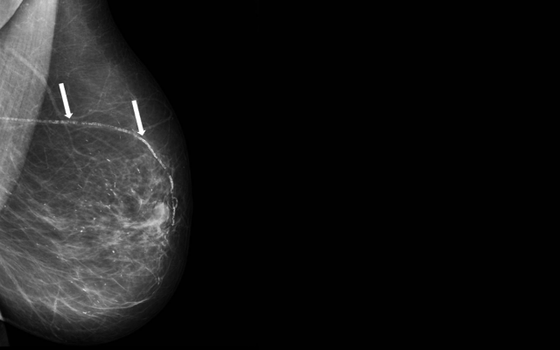

By harnessing cutting-edge artificial intelligence technology, radiologists can pinpoint and measure the presence of Breast Arterial Calcifications (BAC) during your routine mammogram, enabling them to gauge your risk of heart disease directly through this imaging procedure, all with no additional scans, no extra time, and no added exposure.

While BAC often appears harmless on mammograms, research suggests it can indicate broader vascular changes. If BAC is detected, your provider may recommend follow‑up with a cardiologist or primary care provider to assess cardiovascular risk.

cmAngio® is an FDA-cleared AI tool that identifies the presence or absence of BAC on screening mammograms and highlights it for your radiologist to review.

HeartSafe Mammography uses cmAngio®, an FDA-Cleared Artificial Intelligence (AI) based detection software, to identify the presence or absence of breast arterial calcification (BAC) as an incidental finding in FFDM and DBT screening mammograms. The finding indicates whether calcium buildup is present in the breast arterial wall. BAC has been associated with a higher risk of coronary heart or cardiovascular disease, but the presence or absence of BAC alone is not a diagnosis for coronary heart or cardiovascular disease or determinative of a patient’s risk for coronary heart or cardiovascular disease. Results may be used for further patient management at the discretion of a primary care physician, cardiologist, or specialist. If BAC is detected, please consult your primary care physician, a cardiologist, or specialist for further information on diagnosis and treatment. FDA 510(k) Submission #K232367.